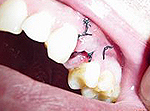

Появления острой боли на 3-5 день после экстракции зуба и затянувшийся процесс заживления лунки являются основными признаками альвеолита. Хронический альвеолит может выявиться во время профилактических осмотров, когда на месте давно удаленного зуба имеется совершенно пустая без грануляционных тканей лунка, на ее дне нередко видна кость. Выявить наличие изменений тканей и подтвердить диагноз альвеолита помогает рентгенография или радиовизиография области удаленного зуба.